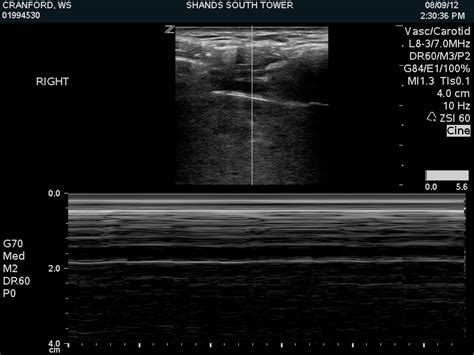

A pneumothorax separates the visceral and parietal pleura, eliminating normal lung sliding between these layers on lung us. Once you understand these basic lung ultrasound findings you will be able to interpret just about any lung ultrasound images. When m mode is used on a normal lung, the lung (and the air inside it) moves back and forth across this single ultrasound beam creating a picture that is often compared to a sandy beach. Unless the pneumothorax is loculated or there are adhesions, the gas moves freely within the thoracic cavity. There is normal lung sliding on the right side. Lung ultrasound pathology profiles such as pneumothorax, pneumonia, cardiogenic pulmonary edema, etc will have a different combination and distribution of these pathological lung ultrasound findings/signs. Nov 08, 2017 · primary spontaneous pneumothorax: 3 article feature images from this case Ein pneumothorax (gelber pfeil) mit noch geringer. To evaluate for pneumothorax with ultrasound, have the patient lay supine. In the supine trauma patient, this will typically be the anterior chest wall lateral to the sternum in the second intercostal space. Among 302 analyzable controls, 65 had absent lung sliding, 16 of them showed an a line sign, and none showed a lung point. Each site was scanned twice at each time point.

Ruling out a pneumothorax is the easy part for me, and it doesn't require much more than a quick visual inspection. Ultrasound can also allow semiquantitative assessment of pneumothorax size by assessing the position of the lung point. Once you understand these basic lung ultrasound findings you will be able to interpret just about any lung ultrasound images. · february 14, 2020 · 1 min read. Nov 08, 2017 · primary spontaneous pneumothorax: Ultrasound use may therefore obviate the need for ct in a majority of cases. Additionally, it can result in timely diagnoses specifically in neonatal pneumothorax. The probe should be oriented perpendicular to the ribs (usually marker dot towards the head). You can also use m mode, or motion mode, which provides an image showing tissue motion along a single ultrasound beam. Unless the pneumothorax is loculated or there are adhesions, the gas moves freely within the thoracic cavity. At its heart, the concept behind using ultrasound to evaluate for air in the space between the visceral and parietal pleura is straightforward. Ultrasound scans in all 43 examinable patients with pneumothorax showed absent lung sliding, 41 of 43 patients had the a line sign, and 34 exhibited a lung point. Ultrasound outperforms cxr in evaluation of pneumothorax in blunt trauma patients, but there cite this article as:

Nov 08, 2017 · primary spontaneous pneumothorax: Ultrasound outperforms cxr in evaluation of pneumothorax in blunt trauma patients, but there cite this article as: Lack of ionizing radiation and easy operation are benefits of this imaging technique. 1 traumatic pneumothorax is common in dogs, whereas spontaneous pneumothorax is relatively rare. In the supine trauma patient, this will typically be the anterior chest wall lateral to the sternum in the second intercostal space. When m mode is used on a normal lung, the lung (and the air inside it) moves back and forth across this single ultrasound beam creating a picture that is often compared to a sandy beach. To evaluate for pneumothorax with ultrasound, have the patient lay supine. A pneumothorax separates the visceral and parietal pleura, eliminating normal lung sliding between these layers on lung us. Among 302 analyzable controls, 65 had absent lung sliding, 16 of them showed an a line sign, and none showed a lung point. Since then there have been many studies that have shown bedside ultrasound can rapidly detect pneumothorax, helping avoid serious potential consequences (i.e. These are the thoracic radiographs: Thoracic ultrasound has more sensitivity than a supine chest radiograph (see: Identification of a lung point on lung us yields 100% specificity for pneumothorax (58).